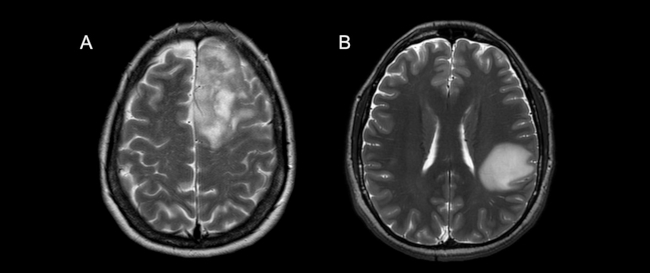

El grado de infiltración cortical fue considerado como la relación entre el perímetro total del tumor y la corteza con alteración de señal en secuencias ponderadas en T2 en comparación a la corteza homóloga contralateral, determinando de forma subjetiva un compromiso mayor o menor al 50% (►Fig. 3).